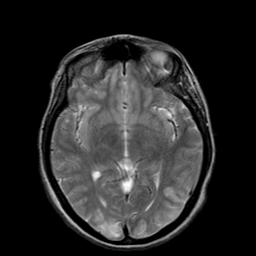

Hypertensive Encephalopathy, overlay -- Slice #11

[Home][Help][Clinical] Slice 11